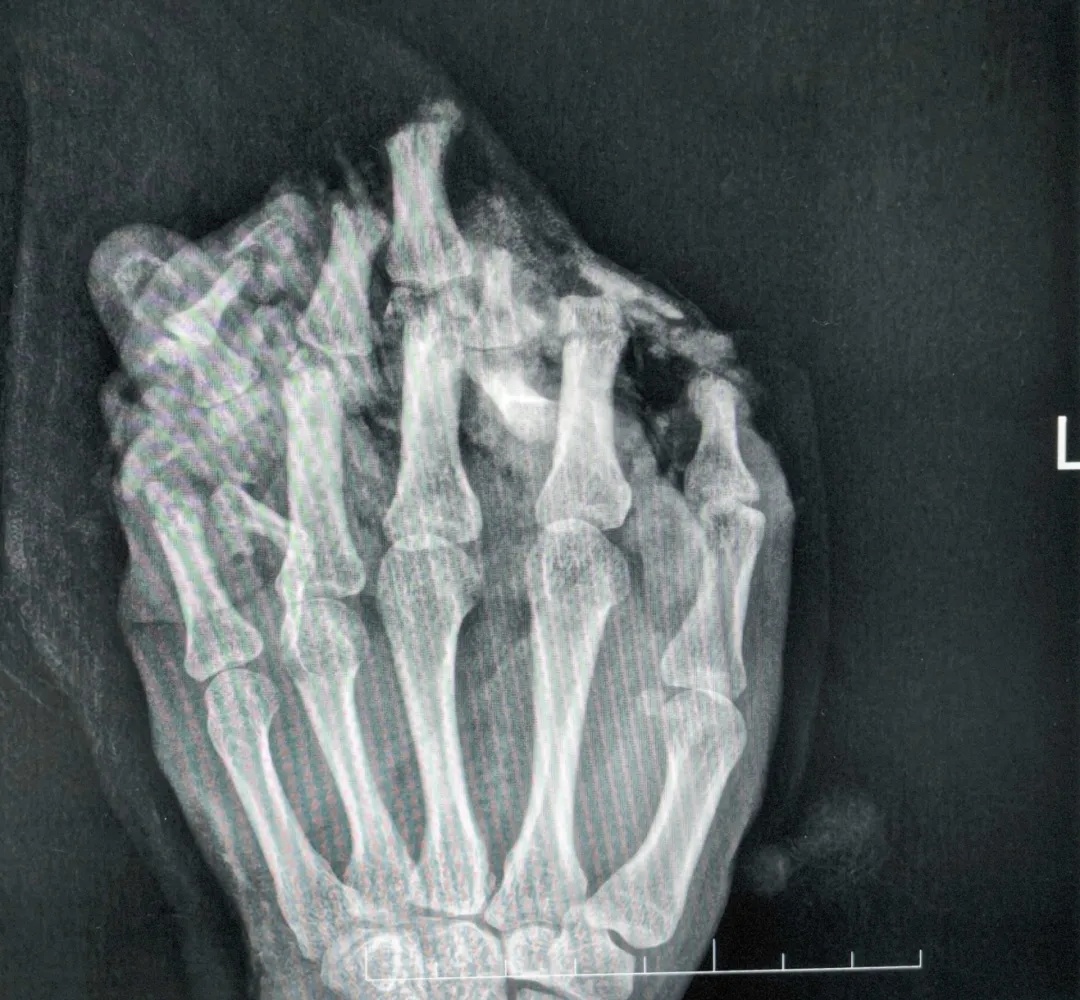

△拍片显示左手伤情严重

医生诊断他为:

①左手掌、手背,示指中指环指小指掌侧及背侧皮肤毁损脱套伤;

②左手掌、手背及各指肌腱神经血管损伤;

③左手多发性开放性指骨骨折伴毁损;

④左拇指末节指腹皮肤、软组织缺损;

⑤左拇指指固有神经断裂;

⑥左拇指甲床裂伤。